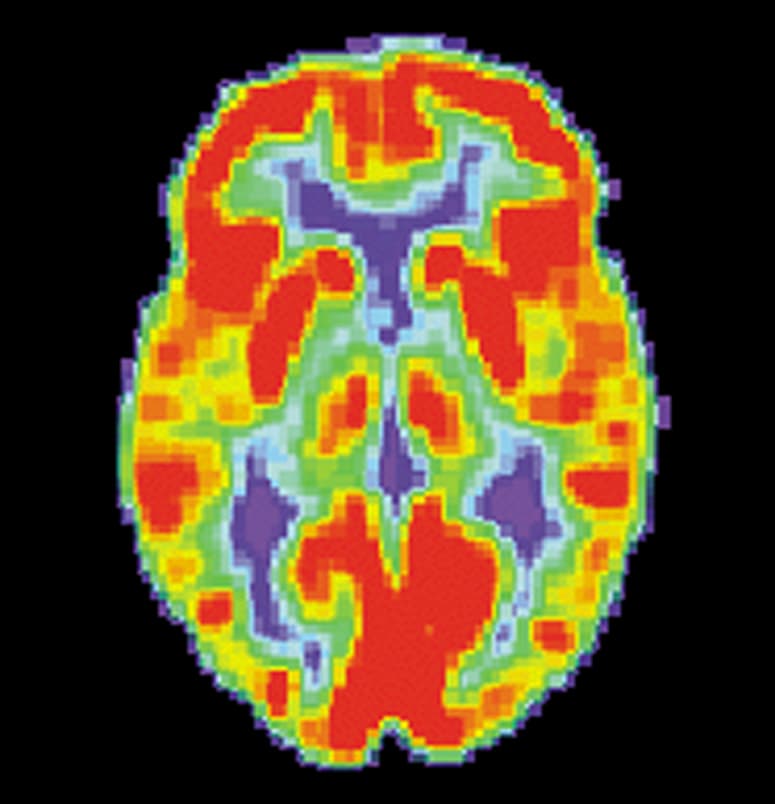

Brain positron emission tomography is a form of positron emission tomography (PET) that is used to measure brain metabolism and the distribution of exogenous radiolabeled chemical agents throughout the brain. PET measures emissions from radioactively labeled metabolically active chemicals that have been injected into the bloodstream. The emission data from brain PET are computer-processed to produce multi-dimensional images of the distribution of the chemicals throughout the brain. The positron emitting radioisotopes used are usually produced by a cyclotron, and chemicals are labeled with these radioactive atoms. The radioisotopes used in clinics are normally 18F (fluoride), 11C (carbon) and 15O (oxygen). The labeled compound, called a radiotracer or radioligand, is injected into the bloodstream and eventually makes its way to the brain through blood circulation. Detectors in the PET scanner detect the radioactivity as the compound charges in various regions of the brain. A computer uses the data gathered by the detectors to create multi-dimensional (normally 3-dimensional volumetric or 4-dimensional time-varying) images that show the distribution of the radiotracer in the brain following the time. Especially useful are a wide array of ligands used to map different aspects of neurotransmitter activity, with by far the most commonly used PET tracer being a labeled form of glucose, such as fluorodeoxyglucose (18F). The greatest benefit of PET scanning is that different compounds can show flow and oxygen, and glucose metabolism in the tissues of the working brain. These measurements reflect the amount of brain activity in the various regions of the brain and allow to learn more about how the brain works. PET scans were superior to all other metabolic imaging methods in terms of resolution and speed of completion (as little as 30 seconds), when they first became available. The improved resolution permitted better study to be made as to the area of the brain activated by a particular task.